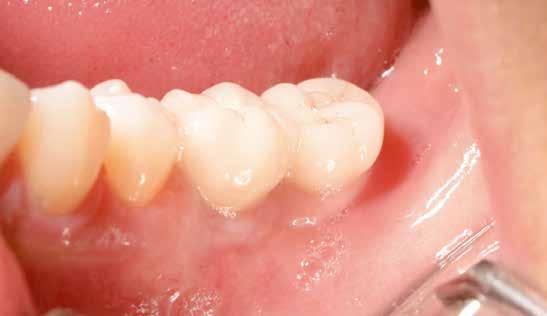

A sebészeti eljárás

Mind a hat implantátum esetén kétlépcsős műtétet végeztünk. Minden sebészeti eljárást bódítás, illetve preoperatív szisztémás antibiotikus terápia nélkül végeztünk. A négy eset közül kettőnél leukocitában és vérlemezkében gazdag fibrint (L-PRF) alkalmaztunk a beavatkozás során (IntraSpin, BioHorizons; 2. táblázat). Minden esetben a pontos CERALOG menetvágási (maximum 15 ford./perc) és fúrási (maximális fúrási fordulatszám: 550–800 ford./perc) protokollt követtük. Az összes implantátumot manuálisan helyeztük be 35 Ncm maximális nyomatékkal. Az implantátumokba PEEK zárócsavar került (2. ábra). A lágyszövetet atraumatikus, felszívódó varrattal, szorosan zártuk/összevarrtuk. A műtétek után szövődmények nem jelentkeztek. A pácienseket arra kértük, hogy a műtét utáni héten naponta kétszer öblögessenek klórhexidinnel (PERIO-AID, 0,05%, DENTAID). Az alsó állcsontnál három hónapos, a felső állcsontnál öt hónapos gyógyulási időt vettünk figyelembe. Három hónap (1. eset) és öt hónap (2., 3. és 4. eset) elteltével a műtétek második stádiumát helyi érzéstelenítés mellett végeztük. A gyógyu-

lási csavarokat (PEEK titáncsavarral) maximum 15 Ncm-rel húztuk meg (3–6. ábra). Az összes implantátum kiváló stabilitást mutatott (a mérésekhez Periotestet használtunk, a Medizintechnik Gulden jóvoltából), és teljesen osszeointegrálódott. Ezt a radiológiai vizsgálatok is megerősítették.

tottuk (az okklúziós koncepciók alapján az implantációs pótlások nem voltak vezető fogak, és csak könnyű érintkezéseket alakítottunk ki, amelyeket artikulációs papírral ellenőriztünk). A páciensek instrukciókat kaptak a megfelelő szájhigiénére vonatkozóan, összpontosítva a fogköz kefékkel történő tisztítására. Végső kontroll röntgenfelvétel készült. A PEEK felépítmény nem radioopák, így az implantátum és a korona közötti távolság könnyen meghatározható a röntgenfelvételen: a felépítmény megfelelően illeszkedik az implantátumban, ha az implantátum válla és a korona alsó széle közötti rés 0,55 mm a röntgenfelvételen (8–11. ábra)